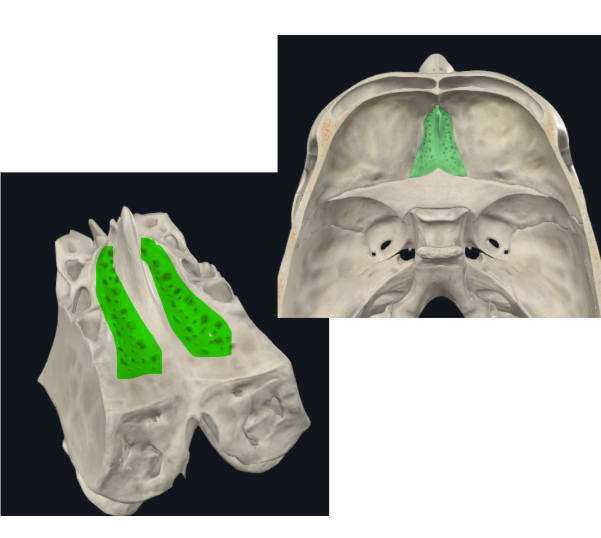

Lámina vertical del etmoides

Lámina perpendicular del etmoides

Forma parte del tabique de separación de ambas fosas nasales (septum/tabique nasal)

Apófisis crista galli por arriba de la lámina horizontal

Apófisis crista galli

Triangular, borde anterior bajo articula con el hueso frontal y completan el agujero ciego(foramen cecum) entre surcos

Laberintos Etmoidales

Forma cuboidea

Contiene los cornetes superiores y medios

Forma parte de la pared lateral de las fosas nasales

Contiene muchas cavidades neumáticas

Celdillas etmoidales, se dividen en anteriores y posteriores

Lámina papirácea en cara lateral